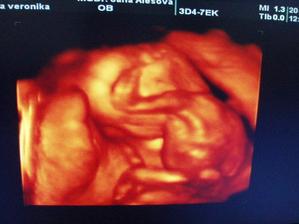

Tak i konečně já přidávám pár svých fotek a postupně budu přidávat další🙂)na prvním utz (fotce) ještě není moc vidět, ale máme srdíčko, jupíííí, zato na druhé už se nám budulínek pořádně ukázal, hip hip hurá🙂))